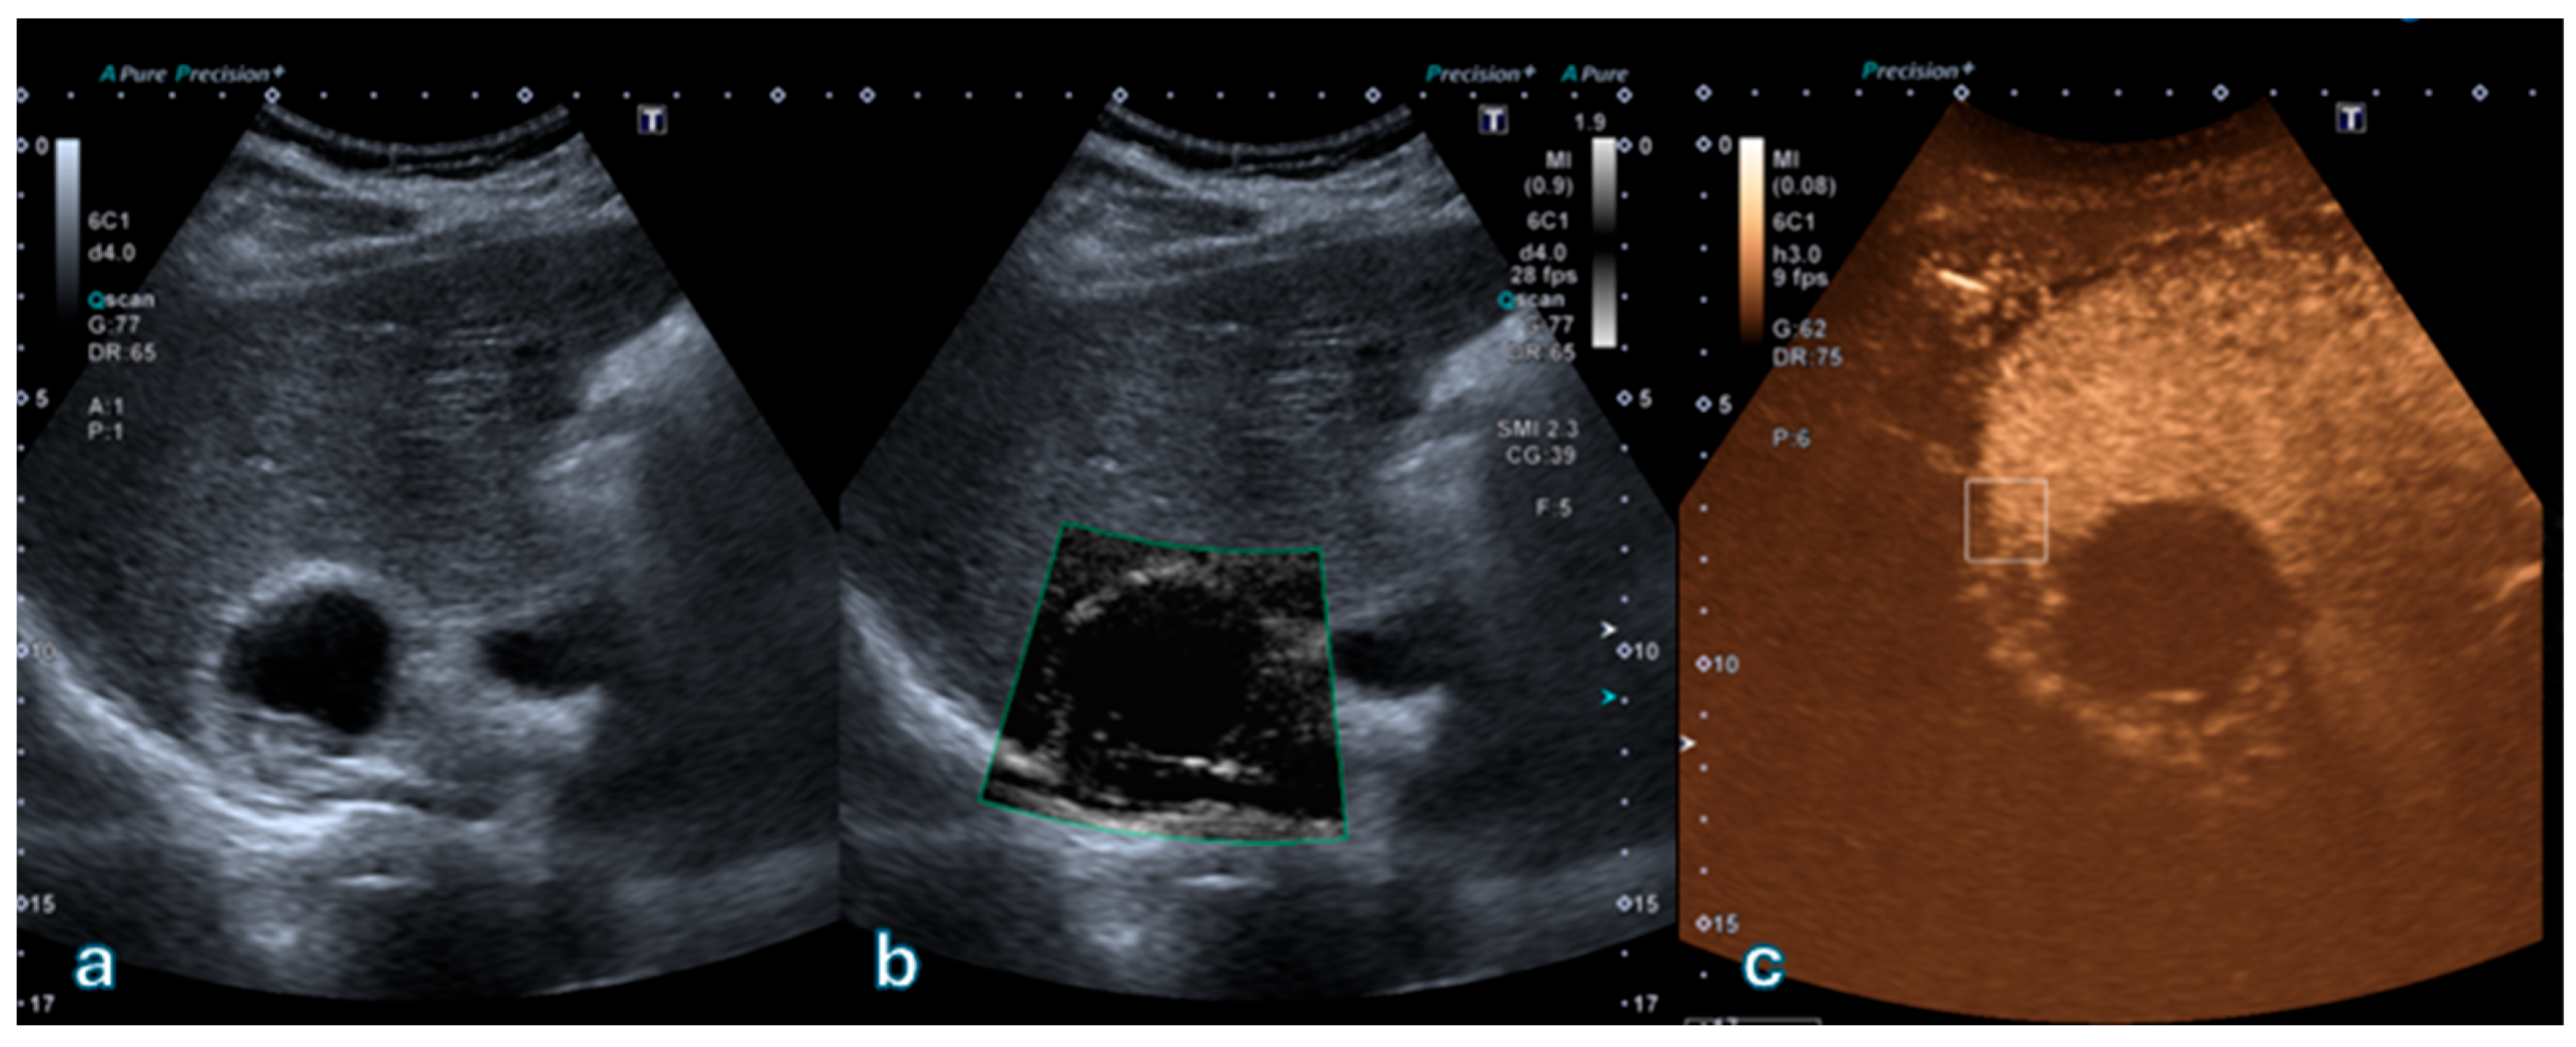

Overall concordance between SMI and CEUS classifications was 80.4% (74 out of 92 lesions). Agreement was perfect for Bosniak I (100%) and II (100%), good for IIF (85%), and moderate for III (68%) and IV (64%) categories. Figure 1 illustrates a representative case of a simple cyst (Bosniak I) with no detectable microvascular flow.

Figure 1. (a) Superb Microvascular Imaging (SMI) of a renal cyst demonstrates no detectable microvascular flow within the thin cyst wall, with absence of septa or mural nodules. (b) Corresponding B-mode ultrasound image shows an anechoic lesion with smooth margins and posterior acoustic enhancement, without any solid components. Overall features are consistent with a simple renal cyst (Bosniak I) according to the 2019 Bosniak classification.